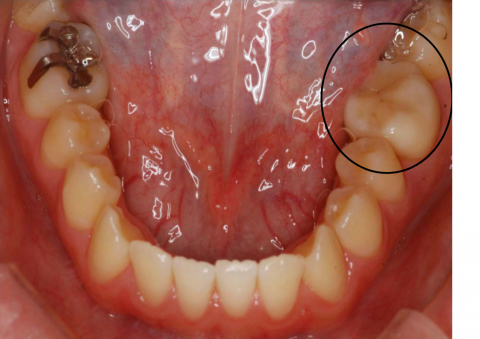

CAD / CAM (Cerec 3D)

CAD / CAMシステムにより様々なマテリアルのミリング(削りだし)を正確に行うことができます。